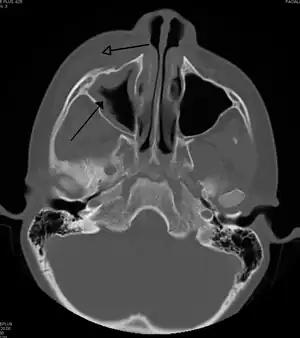

| Periorbital cellulitis caused by a dental infection (also causing maxillary sinusitis) | |

Periorbital cellulitis must be differentiated from orbital cellulitis, which is an emergency and requires intravenous (IV) antibiotics. In contrast to orbital cellulitis, patients with periorbital cellulitis do not have bulging of the eye (proptosis), limited eye movement (ophthalmoplegia), pain on eye movement, or loss of vision. If any of these features is present, one must assume that the patient has orbital cellulitis and begin treatment with IV antibiotics. CT scan may be done to delineate the extension of the infection.

Tests include blood work (CBC) to rule out infectious cause. Also perform a CT scan, x ray of the anterior skull to view the sinuses, MRI scan and finally a soft tissue ultrasound of the orbital region.